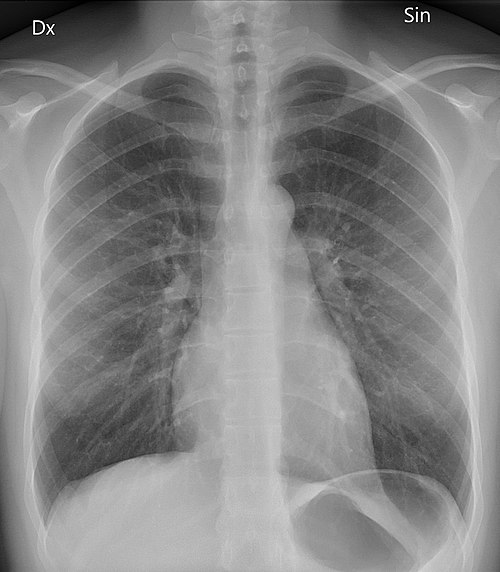

CaptionPosterior-anterior chest radiograph

Chest radiography is the projectional radiographic imaging of the thorax used to assess the lungs, heart, bony thorax, mediastinum, and pleural spaces. It remains a first-line imaging tool across World Health Organization, Centers for Disease Control and Prevention, National Health Service (England), Mayo Clinic, and Johns Hopkins Hospital settings for triage, screening, and ongoing management of cardiopulmonary disease. Clinicians from institutions such as Massachusetts General Hospital, Cleveland Clinic, Mount Sinai Health System, Stanford Health Care, and Karolinska University Hospital rely on chest radiographs to inform decisions in settings ranging from emergency departments to primary care clinics.

Interpretation and Radiographic Signs